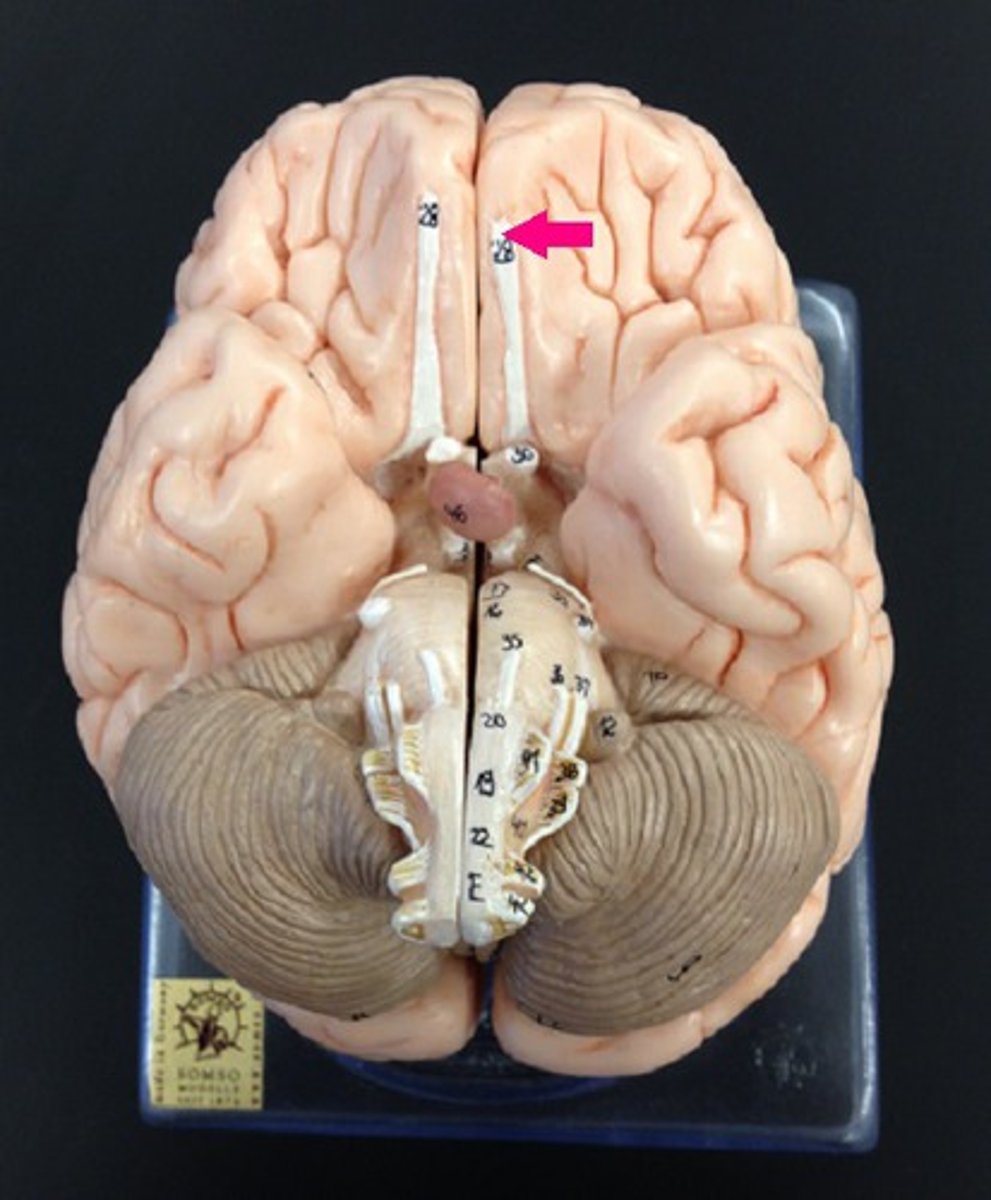

right and left cerebral hemispheres

longitudinal fissure

branches of olfactory nerve (cranial nerve I)

double check this

olfactory bulbs

olfactory tracts

optic nerves (cranial nerve II)

optic chiasma

optic tracts